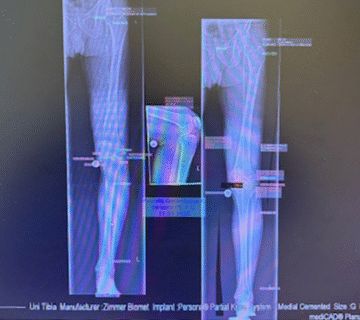

Επέμβαση: Ρήξη μηνίσκου

Μετά από ατύχημα, η Ειρήνη υπέστη ρήξη μηνίσκου στο γόνατο, η οποία της προκαλούσε έντονο πόνο και δυσκολία στη βάδιση.

Απευθύνθηκε στον Δρ. Καλύβα, ο οποίος προχώρησε σε αρθροσκοπική αποκατάσταση, μια ελάχιστα επεμβατική μέθοδο που επιτρέπει ταχεία ανάρρωση και εξαιρετικά αποτελέσματα.